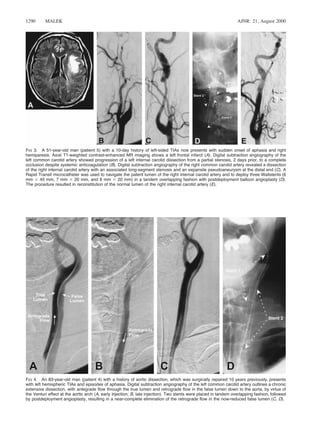

FIG 3. A 51-year-old man (patient 5) with a 10-day history of left-sided TIAs now presents with sudden onset of aphasia and right

hemiparesis. Axial T1-weighted contrast-enhanced MR imaging shows a left frontal infarct (A). Digital subtraction angiography of the

left common carotid artery showed progression of a left internal carotid dissection from a partial stenosis, 2 days prior, to a complete

occlusion despite systemic anticoagulation (B). Digital subtraction angiography of the right common carotid artery revealed a dissection

of the right internal carotid artery with an associated long-segment stenosis and an expansile pseudoaneurysm at the distal end (C). A

Rapid Transit microcatheter was used to navigate the patent lumen of the right internal carotid artery and to deploy three Wallstents (6

mm 3 45 mm, 7 mm 3 20 mm, and 8 mm 3 20 mm) in a tandem overlapping fashion with postdeployment balloon angioplasty (D).

The procedure resulted in reconstitution of the normal lumen of the right internal carotid artery (E).